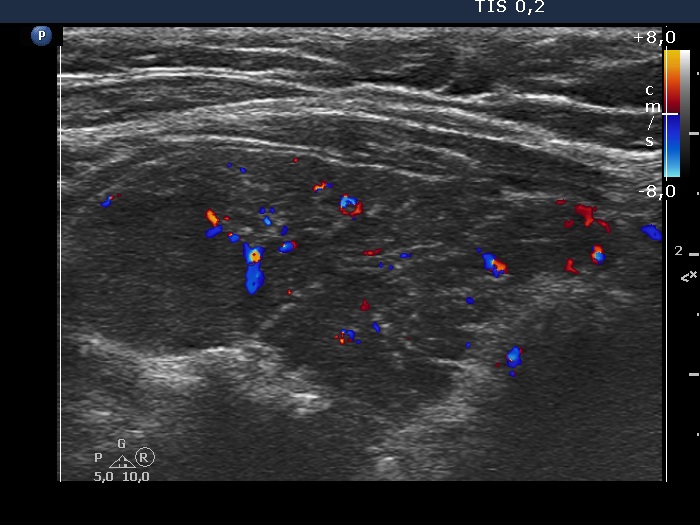

Left lobe, longitudinal scan, color Doppler mode. The vascularization is not specific.